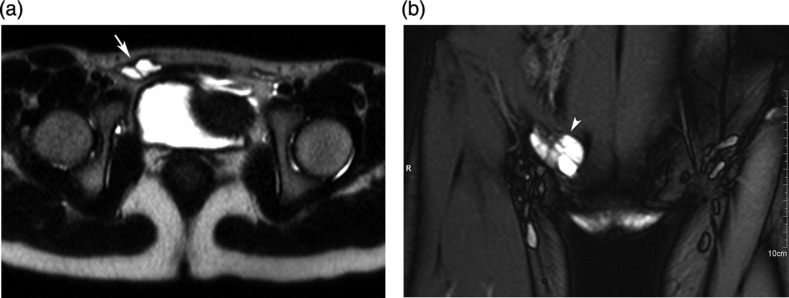

腹股沟管鞘膜积液是一种非常罕见的疾病,它是由于腹股沟管内外翻的腹膜顶骨远端部分形成含液囊而阻塞失败的结果。通常表现为腹股沟无痛性肿胀。超声检查和MRI检查对鉴别腹股沟肿胀有重要作用。我们报告一例5岁女童的影像学表现。

The hydrocele of the canal of Nuck is quite a rare condition and results from the failure of obliteration of the distal portion of evaginated parietal peritoneum within the inguinal canal which forms a sac containing fluid. It generally presents with painless inguinal swelling. Ultrasonography and MRI is plays an important role to differentiate from the other conditions presenting with inguinal swelling. We present the imaging findings of a case in 5-year-old girl.